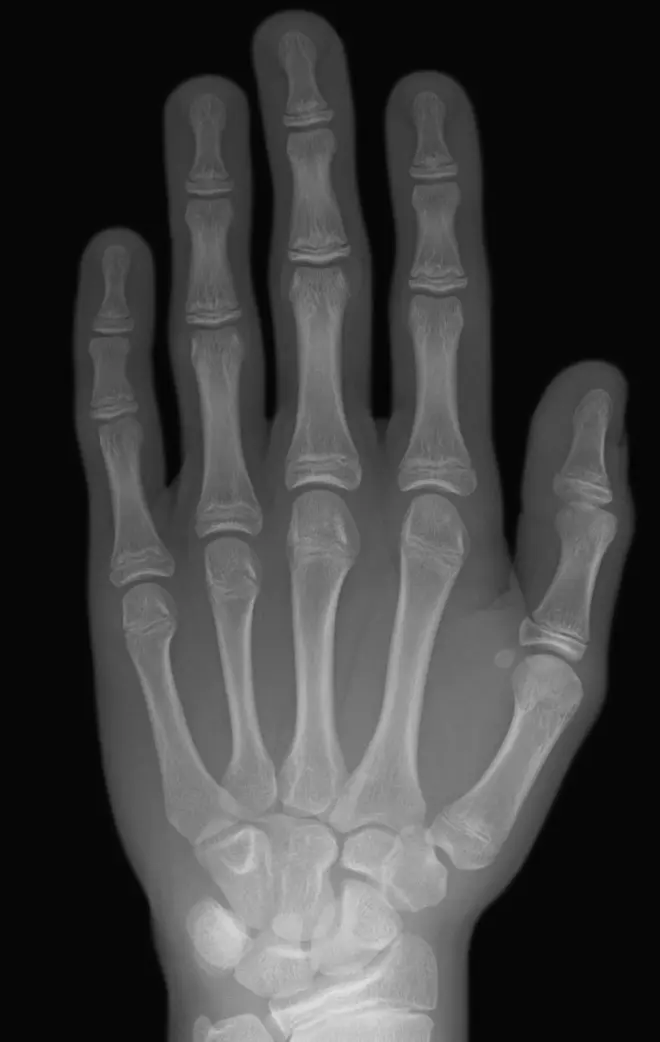

拍骨龄照片(也称为骨龄评估)是一种常见的医学检查方法,用于评估儿童的骨骼成熟度和生长发育情况。这种检查通常使用X射线技术,因此会涉及到一定程度的辐射。

X射线是一种电磁辐射形式,具有穿透物质的能力,并被用于产生影像。在拍骨龄照片时,通过向身体部位照射X射线,从而获得儿童骨骼的影像。然而,需要强调的是,骨龄照片所产生的辐射剂量非常低,通常被认为是安全的。